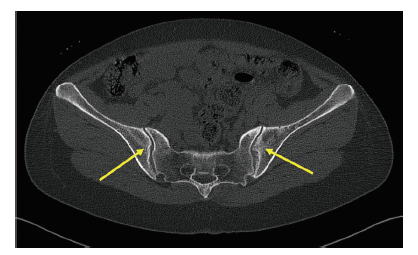

血常规示血红蛋白135 g/L,红细胞4.40×1012/L,白细胞5.99×109/L,淋巴细胞1.23×109/L,中性粒细胞4.20×109/L,血小板282×109/L。ESR 45 mm/h,CRP 32.1 mg/L,IgA 4.2 g/L,IgG 17.2 g/L,HLA-B27阳性,抗核抗体(ANA)、抗可提取性核抗原(ENA)抗体谱、抗心磷脂抗体及中性粒细胞胞浆抗体(ANCA)均为(-),尿常规示尿蛋白(±),尿蛋白定量547 mg/d。气管软骨正位片示气管通畅。骶髂关节CT示双侧骶髂关节间隙略变窄,关节面欠光整,髂骨面密度增高,并见“虫蚀样”改变(图2)。心电图及腹部彩色多普勒超声检查结果均未见明显异常。

图2 一例RP合并AS患者的骶髂关节CT

骨质增生,关节面可见“虫蚀样”骨质破坏